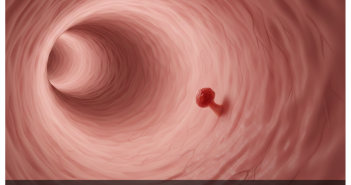

Introduction Colon cancer screening tests are designed to find cancer early or prevent it by…